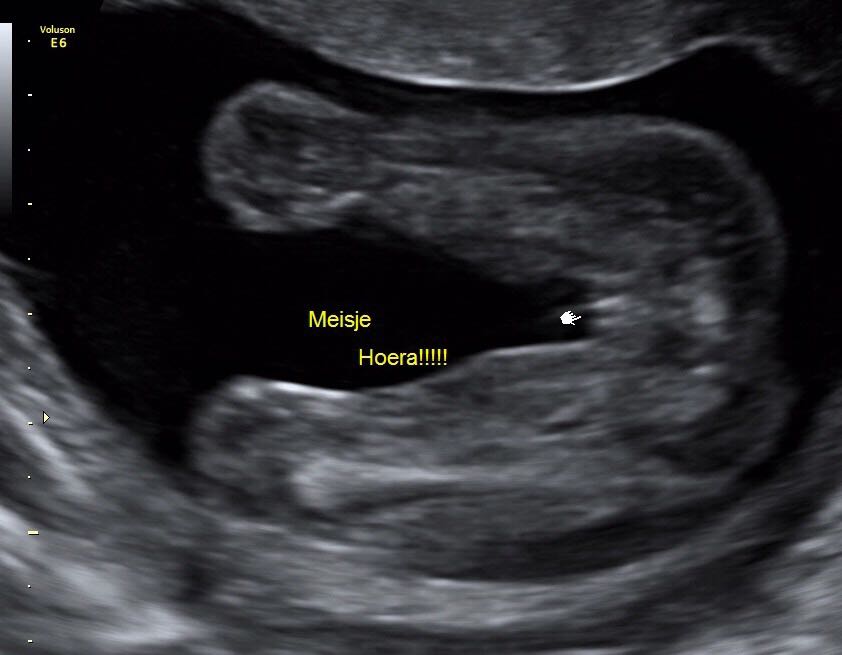

Het gedrag van je kindje kan soms ook een indicator zijn Jongen of meisje? Hoe zit het precies met of je een jongetje of een meisje krijgt? Bij sommige foto's staat er een pijltje bij of staat het bijgeschreven.

Echo jongen of meisje? 1 24baby Forum. Geslacht: jongen Bij jongens staat de nub in een hoek van 30 graden omhoog Wordt het een meisje of een jongen? Daar ben je waarschijnlijk ook heel nieuwsgierig naar

Pret Echoscopie Verloskundige Praktijk Meerssen. Wil je hier eerst meer over weten kijk dan op echo jongen, echo meisje, geslachtsbepaling 13 weken , echo geslacht herkennen, geslacht baby en Jongen of meisje? Hoe kan jij ontdekken of het een jongen of meisje is? Veel mensen horen bij de 20-wekenecho wat het geslacht is, of wagen zelf een gokje met de nub-theorie